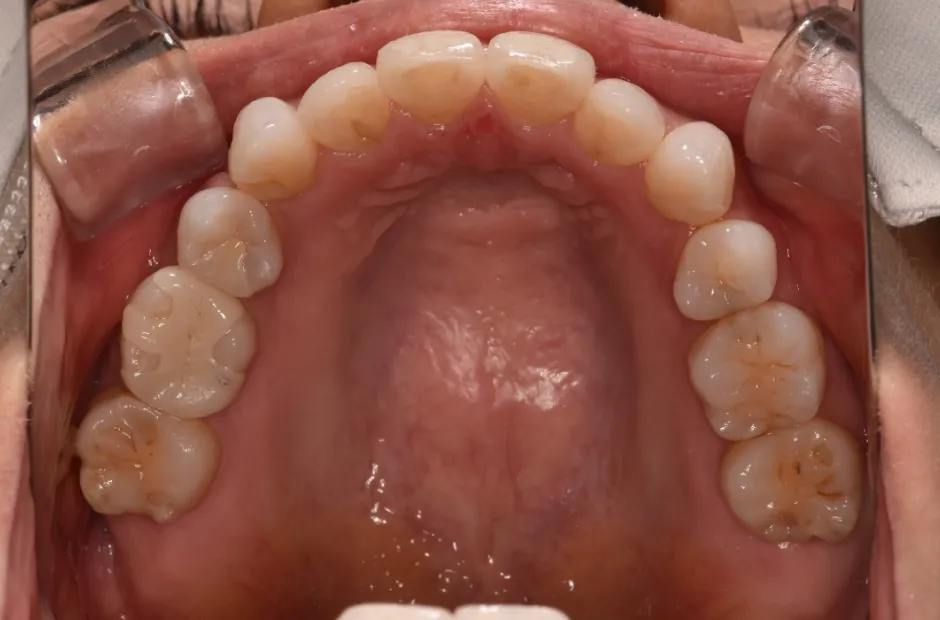

叢生

| 診断名・主訴 | 叢生 |

|---|---|

| 年齢・性別 | 43歳・女性 |

| 治療期間・回数 | 2年7か月 27回 |

| 治療に用いた主な装置 | 舌側矯正 |

| 抜歯部位 | 両顎4,4 |

| 治療費 | 100万円(税抜) |

| リスク・副作用 | 装置による違和感・疼痛・歯肉退縮・歯根吸収・虫歯のリスクなど |

治療前

治療後